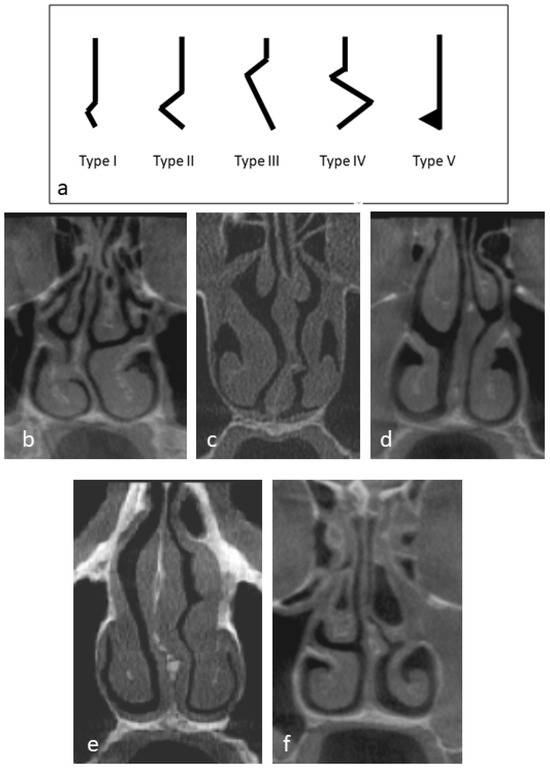

| Nasal septum classification (n = 164) | No nasal septum deviation | 84 | 51.2 | |

| Type I | 15 | 9.1 | ||

| Type II | 16 | 9.8 | ||

| Type III | 34 | 20.7 | ||

| Type IV | 3 | 1.8 | ||

| Type V | 12 | 7.3 | ||